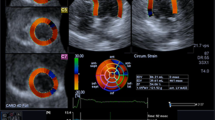

3DSTE imaging was performed from an apical position using a commercial scanner (Artida 4D, Toshiba Medical Systems, Japan) with a fully sampled matrix array transducer (PST–25SX). Wide-angled acquisitions of 4 sub-volumes were acquired over 5 consecutive cardiac cycles during a single breath-hold, resulting in a mean temporal resolution of 23 ± 3 volume per second (range 17–26). Analysis of 3DSTE was done as previously described [6]. The 3DSTE strain data obtained included the three conventional strains (circumferential strain, longitudinal strain, and radial strain). In addition, two new strains, namely 3D strain and area strain, as well as twist were evaluated. 3D strain is a composite parameter of the three conventional strains. Area strain represents the endocardial area change at LV end-systole in relation to its original dimensions at end-diastole. Twist is defined as the maximal rotation seen in the most apical segment minus the maximal rotation seen at the most basal segment of the left ventricle. Fig. 1 depicts the difference between CMR DCE and 3DSTE radial strain in a patient with transmural infarction.

Cardiac magnetic resonance delayed contrast enhancement and three-dimensional speckle tracking echocardiography radial strain in a patient with transmural infarction. a Image of a patient with akinesia and transmural infarction of the septal and anterior walls (>50 % hyperenhancement) and (b) Colour-coded short-axis 3DSTE radial strain image at end-systole, radial strain is decreased as depicted by a blue colour overlay in a comparable region to the hyperenhancement in the CMR DCE, yet this area seems somewhat larger than the DCE one, involving the inferior wall as well. There is reddish colourisation in the other normal contracting segments with no hyperenhancement